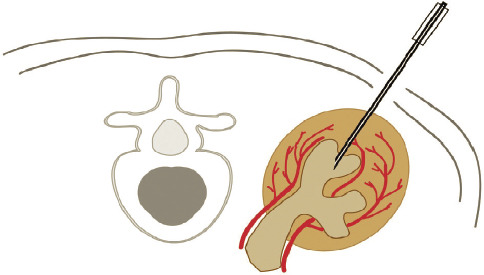

The aim of the present paper is to contribute to the understanding of the history of the anatomical study of the intra-renal arteries. The vasculature and especially the intra-renal arteries of the kidneys are an intriguing field which was first studied through art and then perfected by medicine. Angiography and microsurgery have resulted in partial nephrectomy techniques for surviving kidneys with adequate functional results. Graves' categorization dating from 1954 opened the way for innovative approaches that have resulted in modern topographical anatomy. CONCLUSION: Our understanding of the anatomy of intra-renal arteries has played a significant role in surgical anatomy and internal medicine.